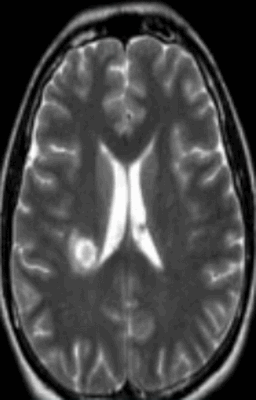

Обычно очаги демиелинизации выглядят как множественные мелкие участки гиперинтенсивного МР-сигнала, расположенные в одном или нескольких отделах головного мозга. По степени их распространенности, давности и одновременности возникновения врач судит о масштабах развития заболевания.

Очаг демиелинизации на МРТ